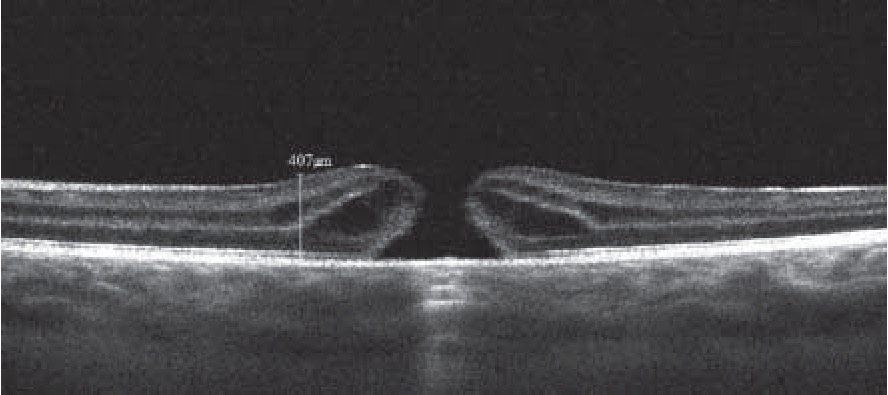

Клинический случай № 2. Пациент Т., 18 лет, обратился в клинику офтальмологии ВМА с жалобами на снижение остроты зрения и наличие темного пятна перед левым глазом, ощущение «искривления прямых линий». Перечисленные нарушения возникли через несколько часов после попадания в глаз с расстояния около 3 м излучения лазерной указки синего цвета. За медицинской помощью обратился только через 6 месяцев после травмы. Тип источника и его характеристики установить не удалось, однако известно, что большинство синих лазерных указок относят к 4 классу лазерной опасности (высокоопасные).

По данным офтальмологического осмотра, острота зрения правого глаза с коррекцией – 1,0. Вспомогательные органы и глазное яблоко без патологии. Острота зрения левого глаза с коррекцией – 0,1 (рефракция миопическая). Вспомогательные органы и передний сегмент глазного яблока без патологии.

Исследование центрального поля зрения выявило абсолютную центральную скотому, которая при офтальмоскопии сопровождалось визуализацией точечного участка белесоватого цвета в макулярной области левого глаза (рис. 3), а СЛО и ОКТ позволили обнаружить в этом же месте разрыв шириной до 400 мкм с утолщенными (более 400 мкм) и кистозноизмененными краями (рис. 4).

Рис. 3. Глазное дно пациента через 6 месяцев после поражения лазерным излучением (лазерной указкой). В центре фовеа определяется округлый дефект сетчатки, острота зрения – 0,1

Рис. 4. Изображение результатов оптической когерентной томографии пациента через 6 месяцев после поражения лазерным излучением (лазерной указкой). В центре фовеа определяется разрыв сетчатки с приподнятыми отечными краями